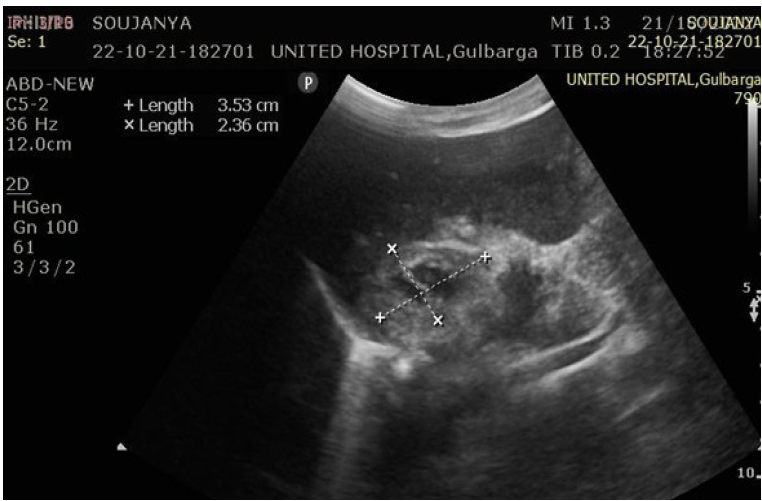

Ultrasonography (USG) evaluation

Ultrasonography was performed to assess adrenal haematomas with respect to site, size, mass effect, and appearance, categorized as early-stage or late-stage haematoma (Figure 1 and 2).